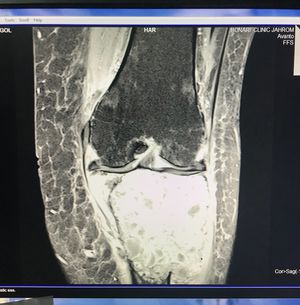

The pt is a 43 years old female who came with cc of a painful firm bulging on her Rt knee , Pain started gradually and gets worse at nights while resting.

She has giant cell tumor on proximal of Rt tibia so that’s why the color is different and also yes the tumor has been affected the medial meniscus and it gets edematus and seems gray,

Actually arthritis is better seen with radiography, this is mri so it’s better not to look around for arthritis, it is giant cell tumor according to her history and both her mri